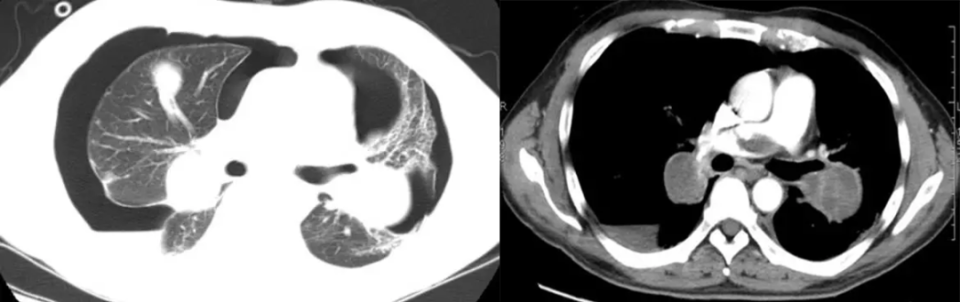

粟粒性转移

粟粒状病灶多见于甲状腺癌、肝癌、胰腺癌及绒毛膜上皮癌转移。常同时伴有纵隔淋巴结肿大及其他脏器转移。

男性,45 岁。左肺上叶肺癌伴双肺粟粒性转移。

肺炎性肺转移

肺炎型的转移病灶边缘模糊不清,可局限于一肺叶或段并伴「充气支气管征」,颇似肺炎样浸润阴影,分布在肺周或肺底等。肺炎型转移特征性不大,需与肺炎区别,明确诊断须靠病理或随访。抗炎治疗无效,化疗后病灶可缩小。部分病灶发展为较大的肿块。肺炎型肺转移的产生机制可能为癌结节浸润生长,结节周围出血或伴癌周阻塞性炎症所致。

男,38 岁。胃腺癌根治术后 4 年。1 年前的胸片显示右上肺片状边缘不清的病灶,怀疑结核,抗结核治疗无效。CT 显示右肺上叶实变应,周围伴磨玻璃密度,内部可见充气支气管征。穿刺活检证实。